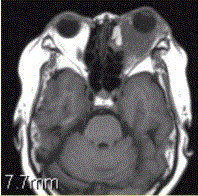

问题 患者女,64岁,左眼突出5年余。查体左眼球前突6mm,眼球运动自如,眼底无异常,下睑扪及边界不清、质软的肿块,视力正常,MR表现如下图。 诊为炎性假瘤,则此例患者的分型应为

选项 A.肿块型 B.弥漫炎症型 C.泪腺型 D.肌炎型 E.眼睑型 F.眼球型

答案 B